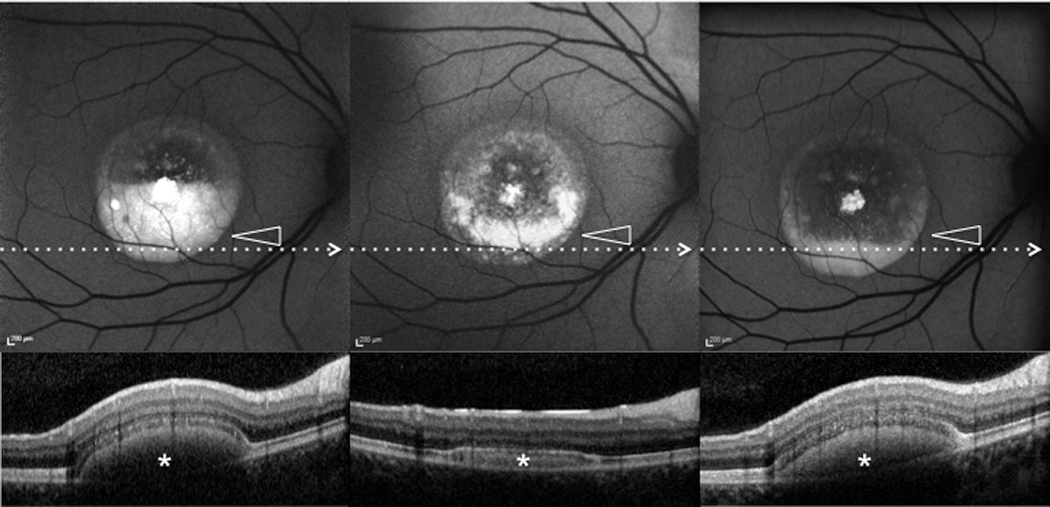

Figure 6. Patient #1.Blue fundus autofluorescence (FAF) and spectral-domain optical coherence tomography (SD-OCT) reveal the right eye

affected with pseudohypopyon lesion at both study entry and last follow-up visit (61 months later). Blue FAF frames and SD-OCT

scans at study entry (top left and bottom right panels) show a partial reabsorption of the hyperautofluorescent (arrowhead)/hyperreflective

material (asterisk) and replacement by a fluid component. During follow-up, blue FAF frames and SD-OCT scans (top middle and

bottom middle panels) show further reabsorption of the hyperautofluorescent (arrowhead)/hyperreflective material (asterisk).

At the last follow-up visit, blue FAF frames and SD-OCT scans (top left and bottom right panels) show development of the hyperautofluorescent

(arrowhead)/hyper-reflective material (asterisk).